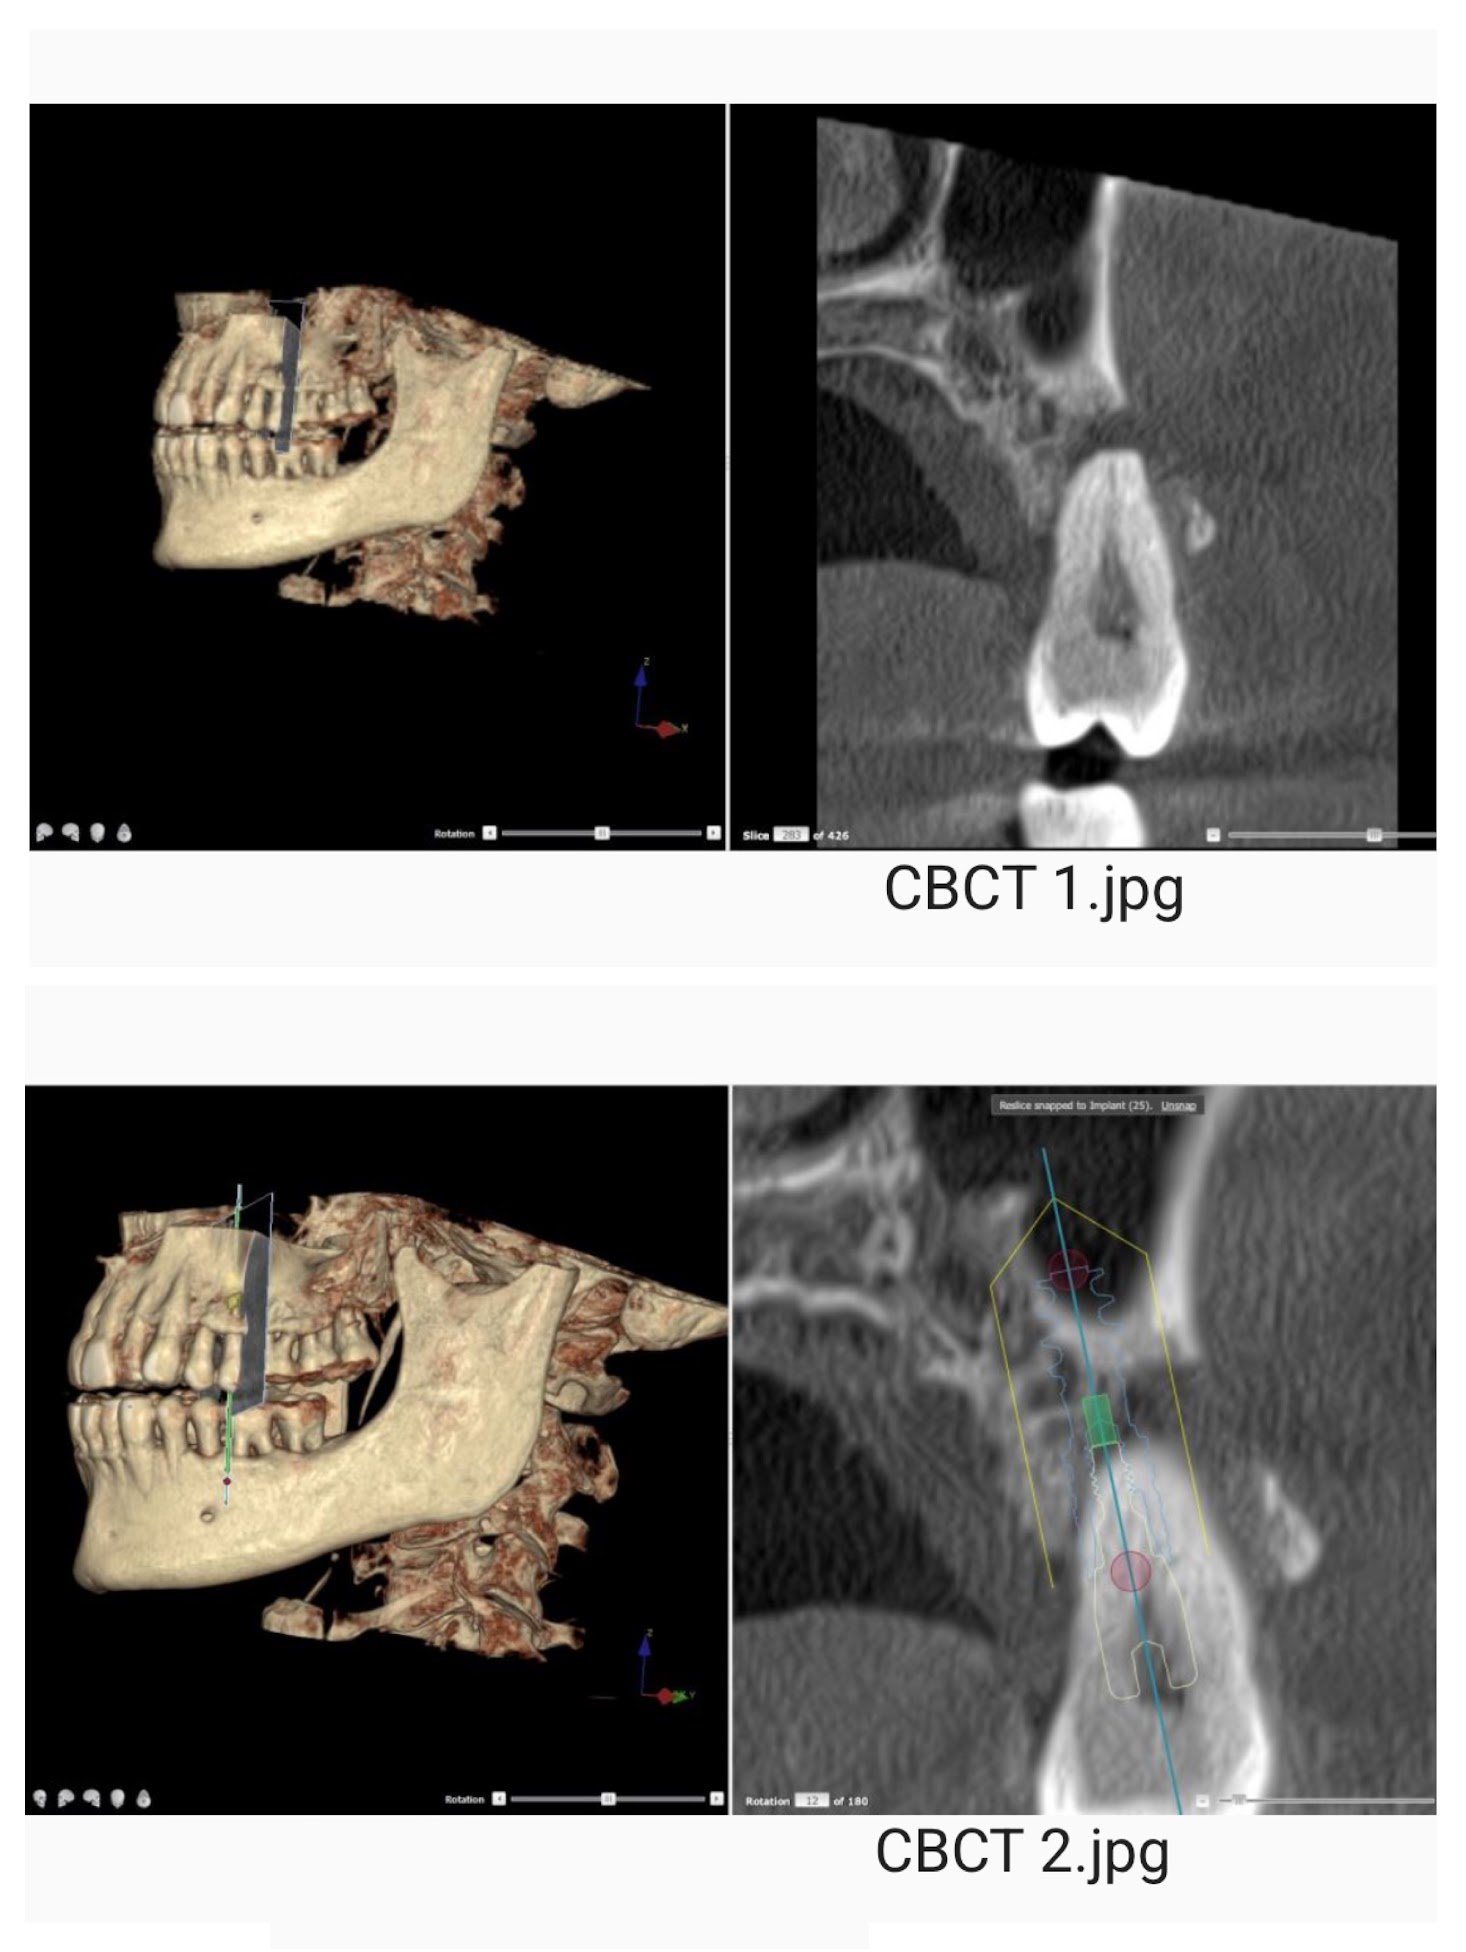

Dental Implants

With the newest technology and products, we can provide a predictable solution for tooth loss.

Implant planning

Implant placement

Extraction of tooth and placement of immediate implant

Implant Planning with CBCT imaging